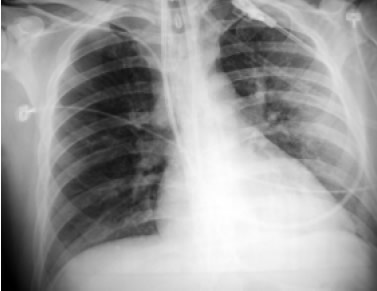

Masculino de 36 años, previamente sano, ocupación policía. Ingresó posterior a herida por proyectil de arma de fuego en pierna izquierda que condicionó fractura de peroné (Figura 1). Presentó crisis convulsivas tónico-clónicas generalizadas, estado confusional, dificultad respiratoria e hipoxemia, por lo que se ingresó a la UTI. A la exploración física con FC de 130/m, FR de 35/m, PA de 100/60, SatO2 al aire ambiente al 70%, Temperatura de 38 ºC. Con estertores crepitantes e hipoaereación bibasal de predominio izquierdo. Presencia de petequias a nivel conjuntival (Figura 2). En la citometría hemática con trombocitopenia de 150,000/mm3. En la Rx de tórax con infiltrado intersticial bibasal de predominio izquierdo (Figura 3). En la angiotomografía computada de tórax se observó infiltrado intersticial y áreas de condensación de predominio basal y no se observaron coágulos en el sistema arterial pulmonar. La resonancia magnética cerebral con imágenes hiperintensas corticales bilaterales (Figura 4).

Figura 3. Radiografía de tórax que muestra infiltrado intersticial de predominio izquierdo.

En relación con el diagnóstico por imagen es importante mencionar que un alto porcentaje de los pacientes con SEG presentan alteraciones en la radiografía de tórax en las primeras 72 h posteriores al traumatismo.11 Los hallazgos son inespecíficos y suelen corresponder a edema pulmonar e infiltrado pulmonar difuso. La TAC cerebral puede mostrar signos sugerentes de embolia grasa como focos de hipodensidad o infartos hemorrágicos localizados, pero en la mayoría de las ocasiones suele ser normal. Los hallazgos de la IRM del enfermo son similares a los descritos en otros artículos, consistiendo en múltiples lesiones hiperintensas en secuencias con TR largo distribuidos predominantemente en la sustancia blanca.12 El número de lesiones se correlaciona con la escala de coma de Glasgow. La restricción de la difusión evidencia el edema citotóxico que permite el diagnóstico precoz, previo a la aparición del edema vasogénico. Estas lesiones son secundarias a la ruptura de la barrera hematoencefálica, probablemente explicada por el efecto químico directo de los ácidos grasos.